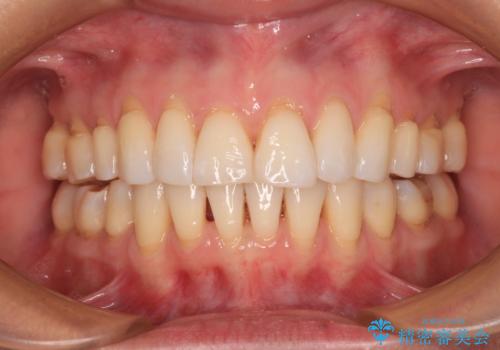

[ インビザライン矯正 ] マウスピースで治す前歯のがたつき

![[ インビザライン矯正 ] マウスピースで治す前歯のがたつきの症例 治療後](https://seimitsushinbi.jp/wp/wp-content/uploads/2023/11/IMG_2993-500x350.jpg?v=1699664953)